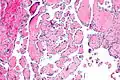

Intravascular papillary endothelial hyperplasia is a rare, benign tumor. It may mimic an angiosarcoma, with lesions that are red or purplish 5-mm to 5-cm papules and deep nodules on the head, neck, or upper extremities.[1][2]: 592

Pathology

Histopathology Images